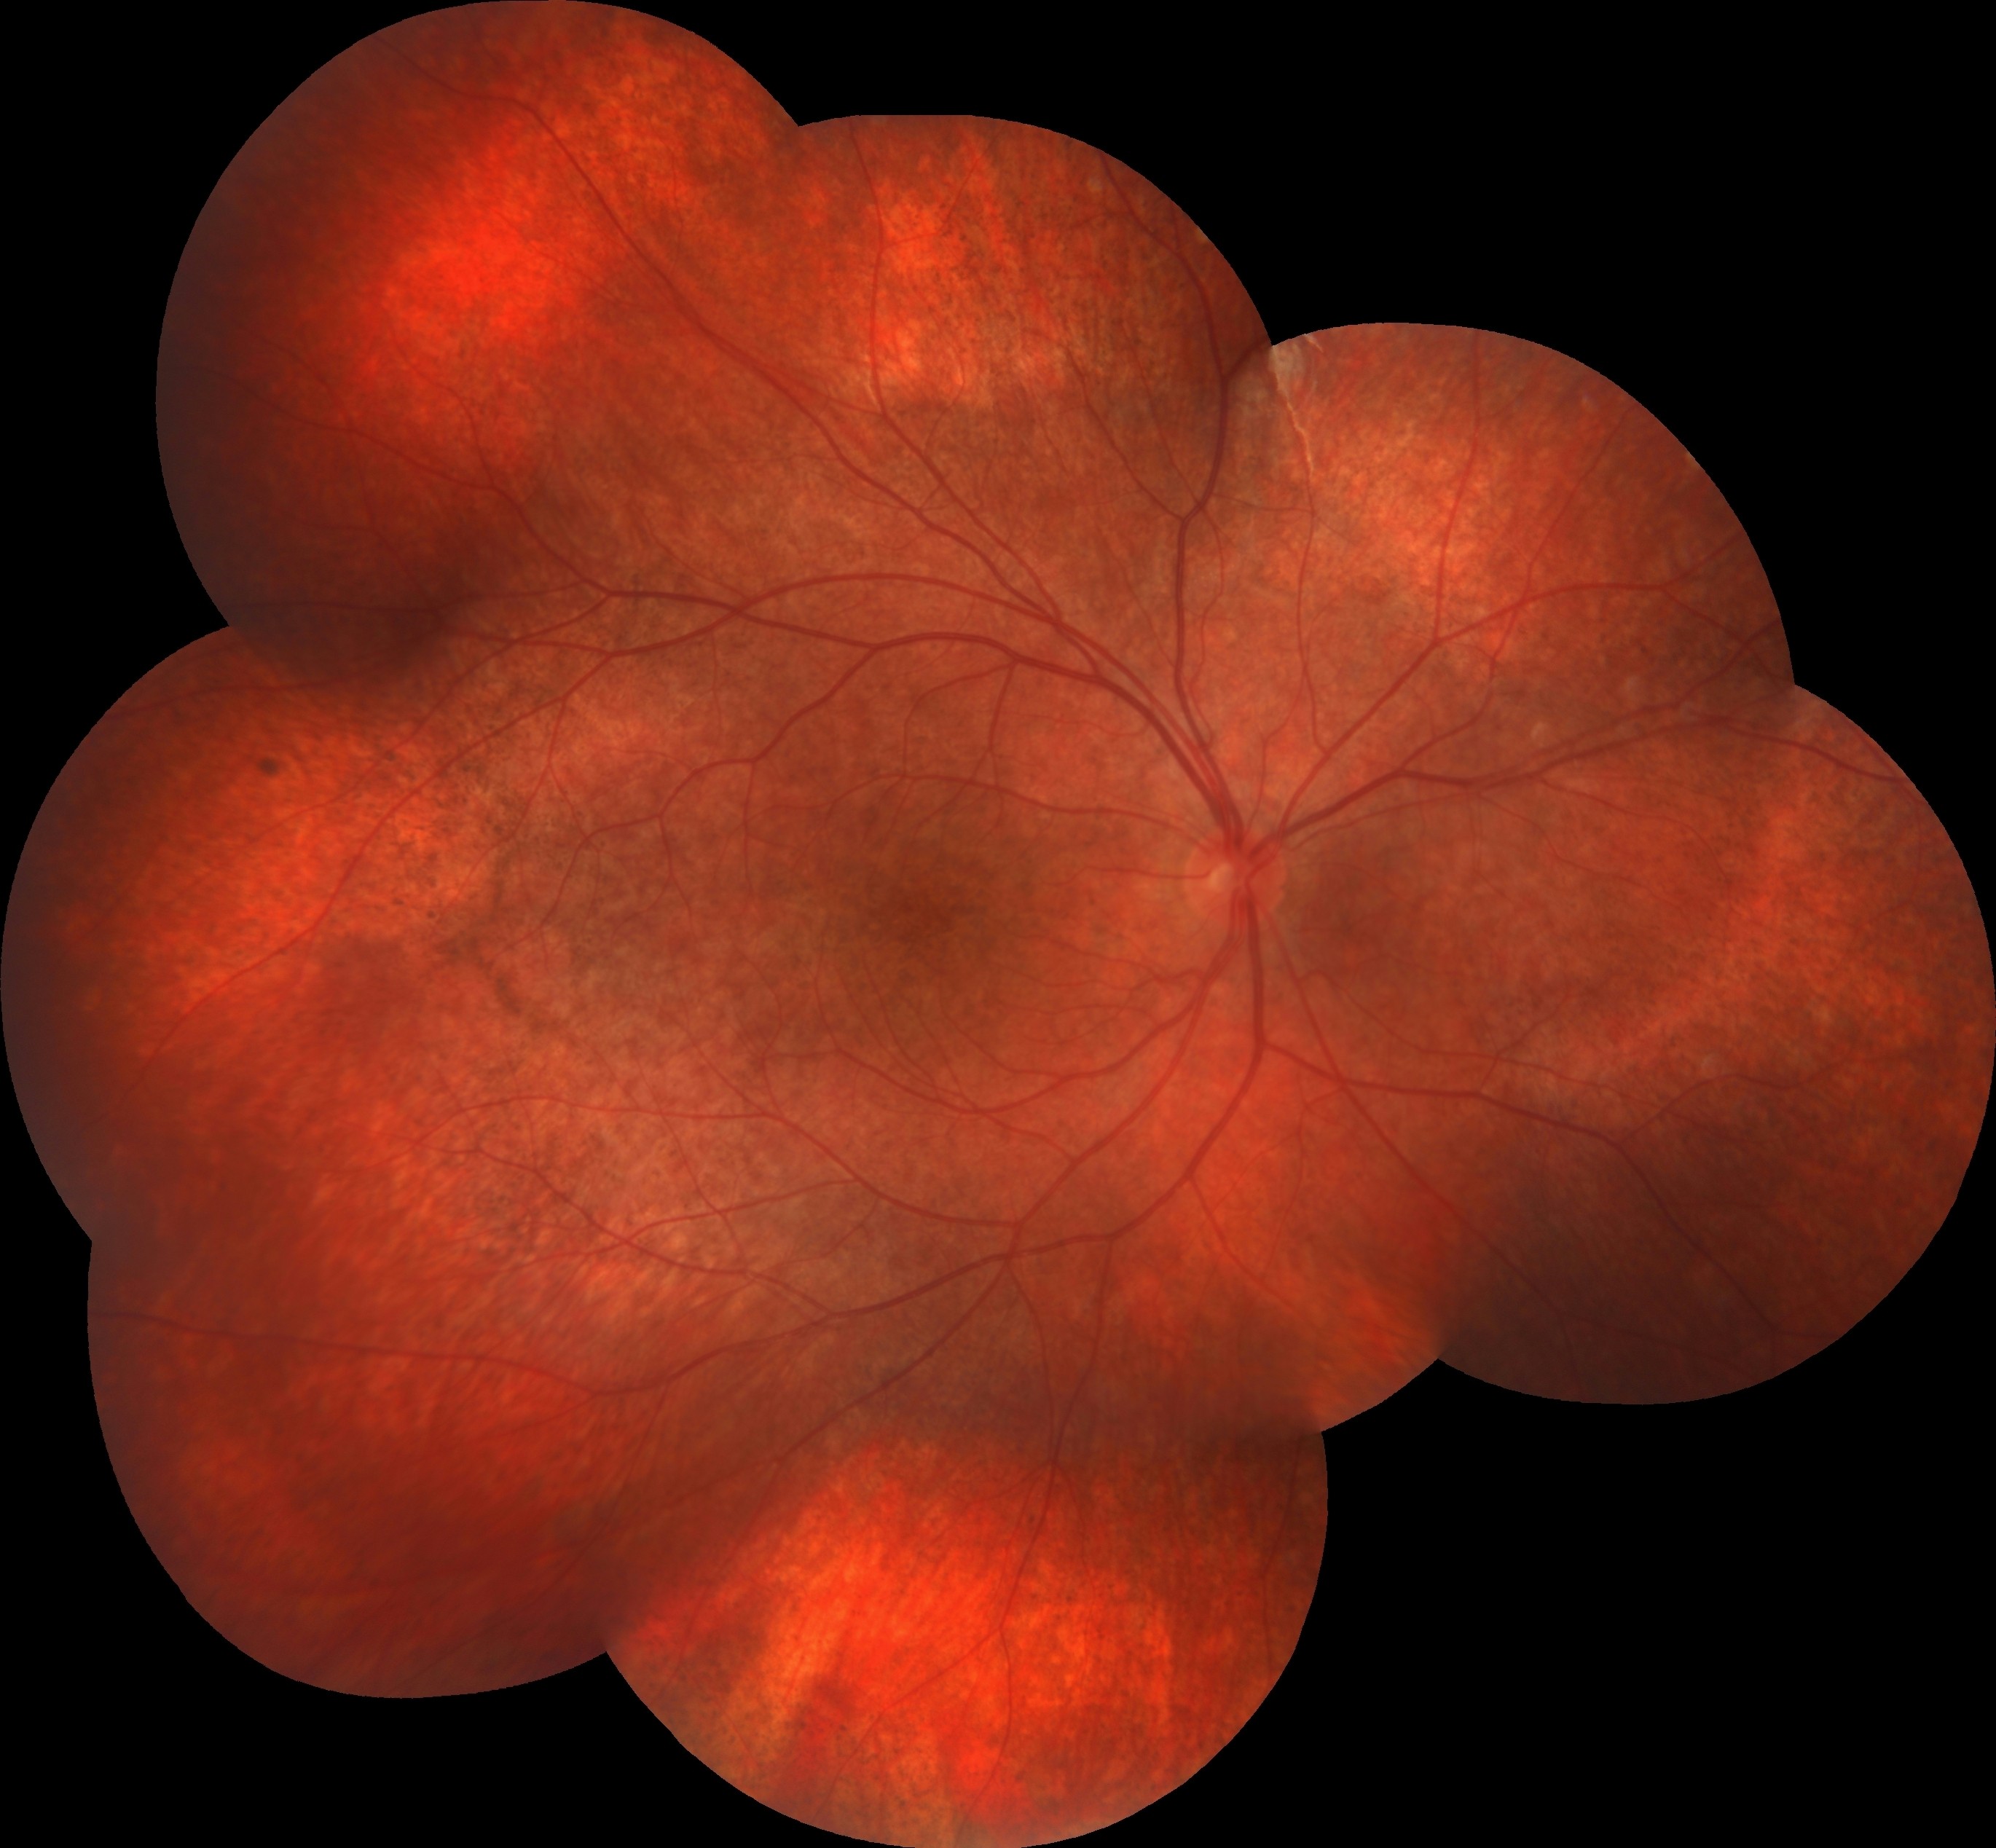

On ocular examination, the BCVA was 20/20 in the right eye and 20/400 in the left eye. IOPs were within normal limits in both eyes and anterior segment examinations were unremarkable. Dilated fundus examination of the right eye revealed a normal optic disk with a classical rubella retinopathy findings — a classic salt-and-pepper appearance of the retina that is due to the distribution of areas of increased and decreased pigmentation. In the left eye, in addition to classical rubella retinopathy findings appearance, a whitish subretinal lesion with retinal hemorrhages in the macula was detected. Mottling of the RPE was also evident in both eyes.

Fundus fluorescein angiography illustrated a pattern of diffuse spotty fluorescence because of the defective RPE without any leakage or staining in the right eye. On the left eye, in addition to diffuse spotty fluorescence, an active subfoveal CNV lesion, that hyperfluoresces in the early phases of the FFA, maintains well-demarcated borders, and leaks, was detected.

Fundus autofluorescence highlighted the fundus abnormalities patchy auto-fluorescence with a stippled hypo-fluorescence in both eyes, and also an hypo-autoflorescence area corresponding to the area of choroidal neovascularization in the left eye.